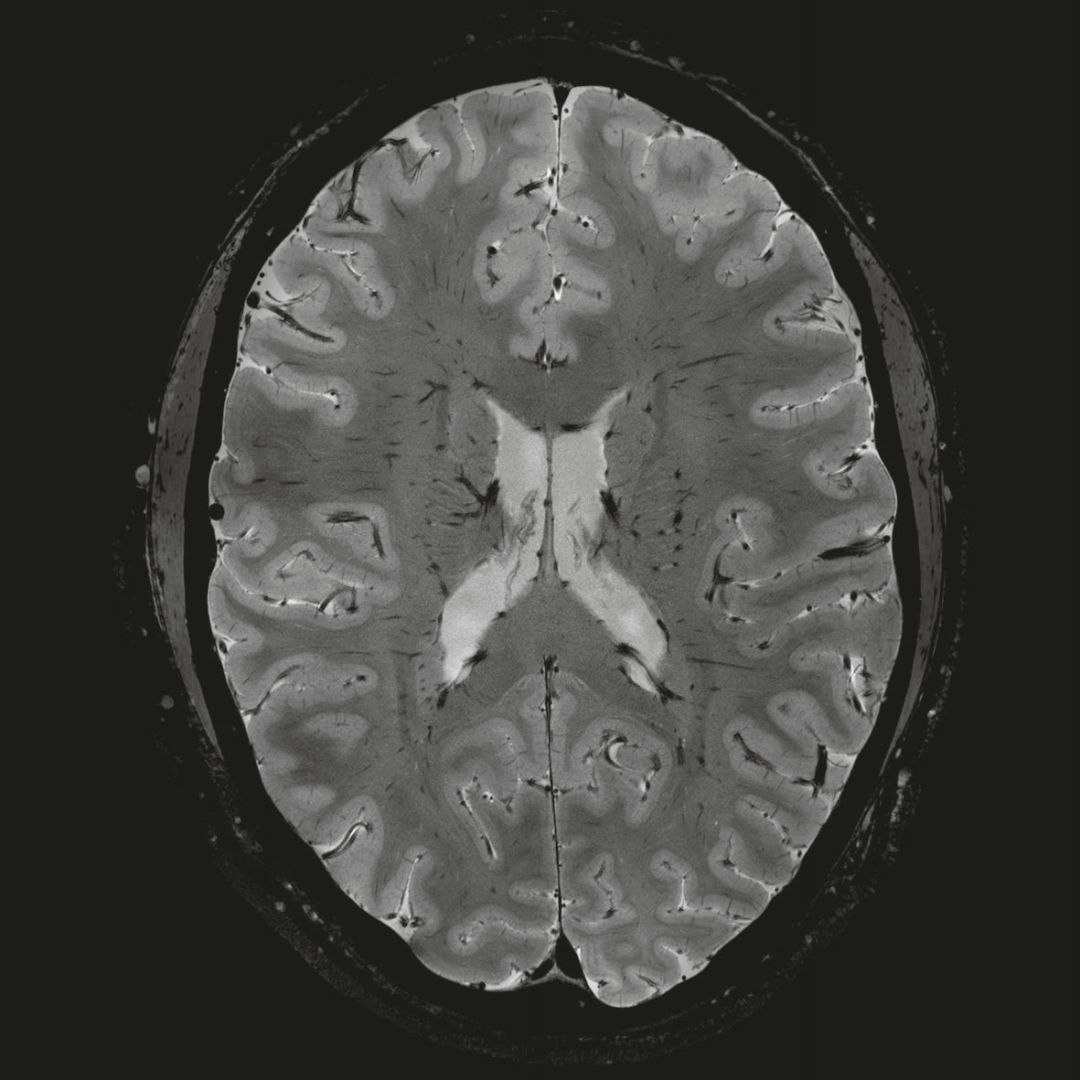

在剛剛結(jié)束的China Med上,西門醫(yī)療首次在中國展出了首臺臨床科研雙模7T磁共振MAGNETOM Terra,大部分現(xiàn)場觀眾也是首次看到這臺號稱“全球首臺可用于臨床的7T磁共振”。

但近年來,西門子與科研機構(gòu)共同研究發(fā)現(xiàn),7T提供了數(shù)倍于傳統(tǒng)3T磁共振的信噪比和空間分辨率,在神經(jīng)、血管、腫瘤、骨關(guān)節(jié)等多個方面都會帶來全新的突破性進展。尤其是在目前常規(guī)影像設(shè)備難以診斷的神經(jīng)退行性疾病如阿茲海默氏病、帕金森病等疾病的發(fā)病機理、早期診斷、治療方案確定以及治療效果評估上,有著極大的潛力。

MAGNETOM Terra在業(yè)界首次實現(xiàn)了兩倍于傳統(tǒng)7T的超強梯度性能,實現(xiàn)超快速、超高效、超高分辨功能磁共振成像。如此高性能的梯度系統(tǒng)無論對于科研還是臨床都帶來了更多可能。

1毫米的各向同性分辨率DTI:神經(jīng)纖維束的交叉細(xì)節(jié)顯示

0.8毫米的各向同性分辨率:精確劃分灰質(zhì)和白質(zhì)

0.8毫米的各向同性分辨率:超精細(xì)的解剖細(xì)節(jié),例:小腦的精細(xì)結(jié)構(gòu)

超精細(xì)的解剖細(xì)節(jié):T2對比

0.17 x 0.17 x 0.8毫米分辨率超高。

(TOF)300微米的各向同性分辨率顯示最小的血管